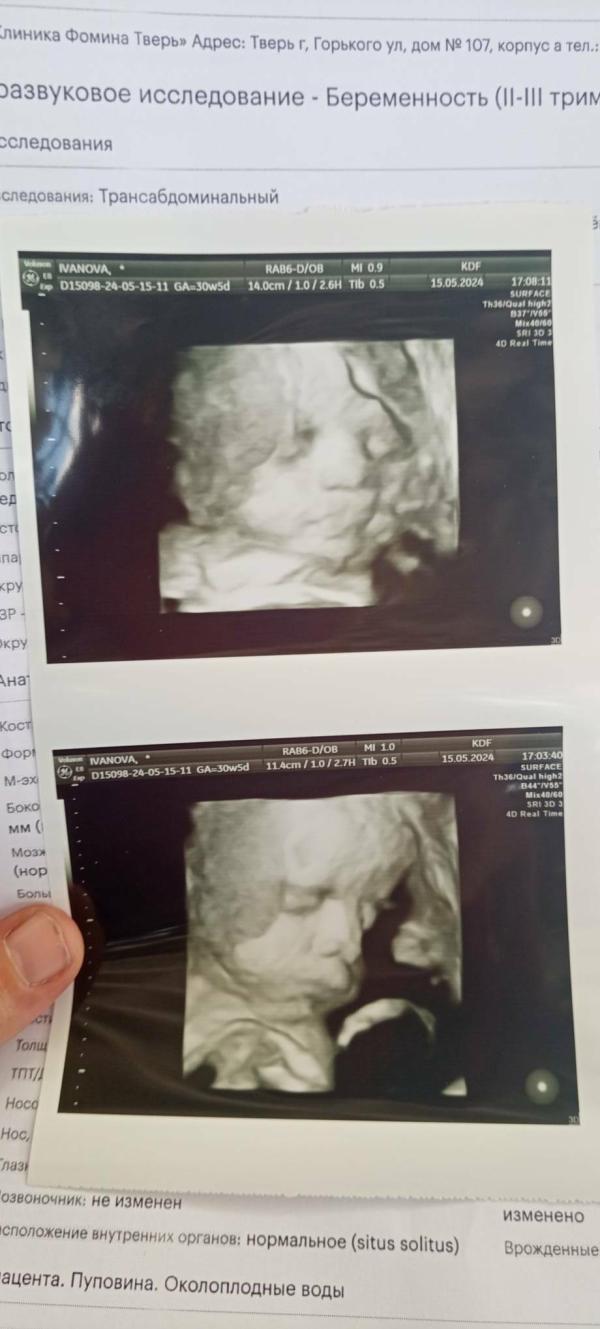

Как же быстро пролетело время))))) Казалось вот только узнала что беременна, а уже бусинка рядом сопит)))) Наслаждайтесь каждым моментом беременности!!! Самое главное не накручивайте себя, если чтото беспокоит сразу к врачу!!!! Сколько помню врача узи просто достала, что не так сразу к ней😝😝😝